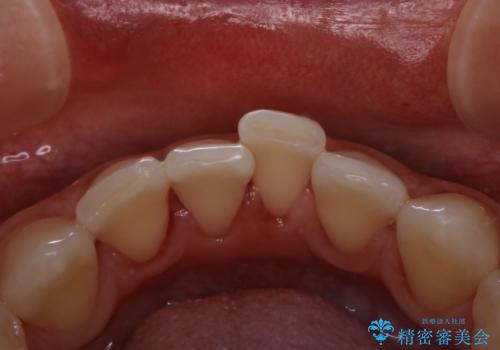

30代男性 虫歯の治療前にPMTC

- 歯医者でのクリーニングはかなり久しぶりで、今後虫歯の治療もしていくので綺麗にしたいとのことでした。PMTC30分コースを行いました。